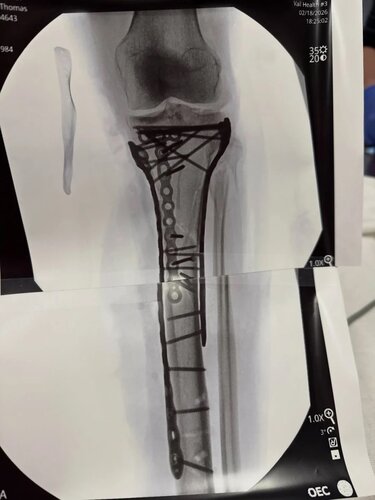

Η 41χρονη Ολυμπιονίκης ενημέρωσε τους διαδικτυακούς της φίλους μέσα από το νοσοκομείο, λίγες ημέρες μετά την επιστροφή της στις Ηνωμένες Πολιτείες. «Τα κατάφερα στο χειρουργείο… κράτησε λίγο περισσότερο από 6 ώρες. Όπως μπορείτε να δείτε, χρειάστηκαν πολλές λάμες και βίδες για να αποκατασταθεί η ζημιά, αλλά ο Δρ. Hackett έκανε εξαιρετική δουλειά», έγραψε σε ανάρτησή της στο Instagram, δημοσιεύοντας βίντεο από τη μεταφορά της με φορείο, φωτογραφία με τα υλικά οστεοσύνθεσης και ακτινογραφίες της κνήμης της γεμάτης μεταλλικά στηρίγματα.